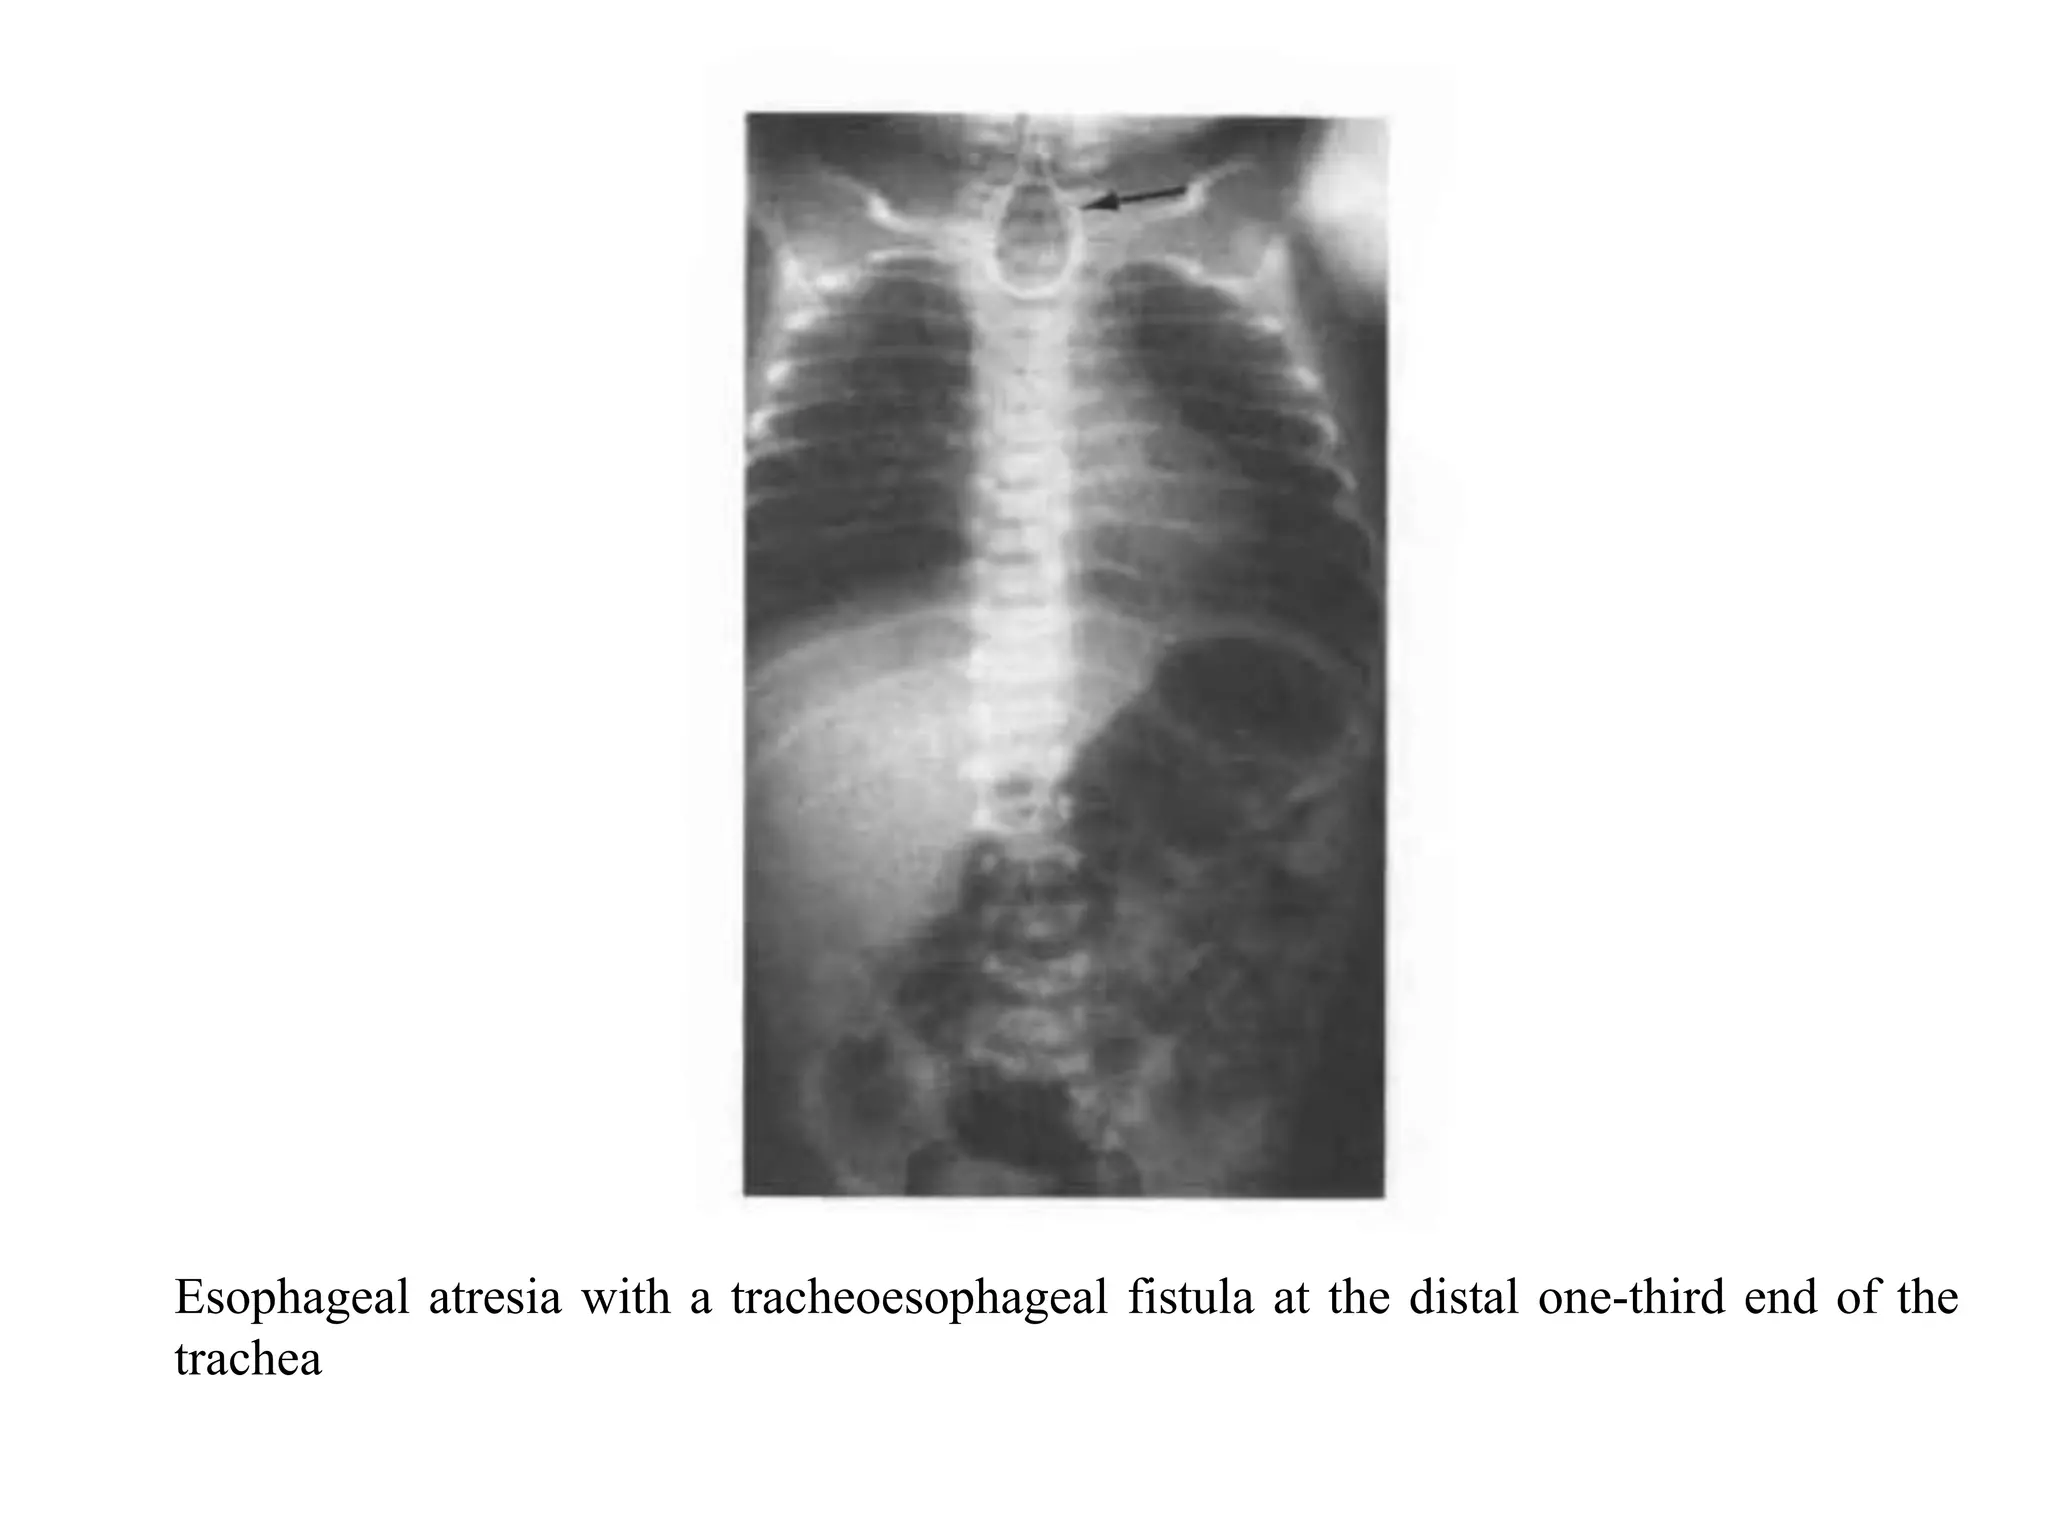

Esophageal atresia with a tracheoesophageal fistula at the

distal one-third end of the trachea. This is the most common

type, occurring in 82% of cases. The anteroposterior (AP)

radiograph (the image on the next slide) of this malformation

shows an enteric tube (arrow) coiled in the upper esophageal

pouch.

The

air

in

tracheoesophageal fistula.

bowel

indicates

a

distal

Esophageal atresia witha tracheoesophageal fistula at the distal one-third end of the trachea. This is the most common type, occurring in 82% of cases. The anteroposterior (AP) radiograph (the image on the next slide) of this malformation shows an enteric tube (arrow) coiled in the upper esophageal pouch. The air in tracheoesophageal fistula. the bowel indicates a distal